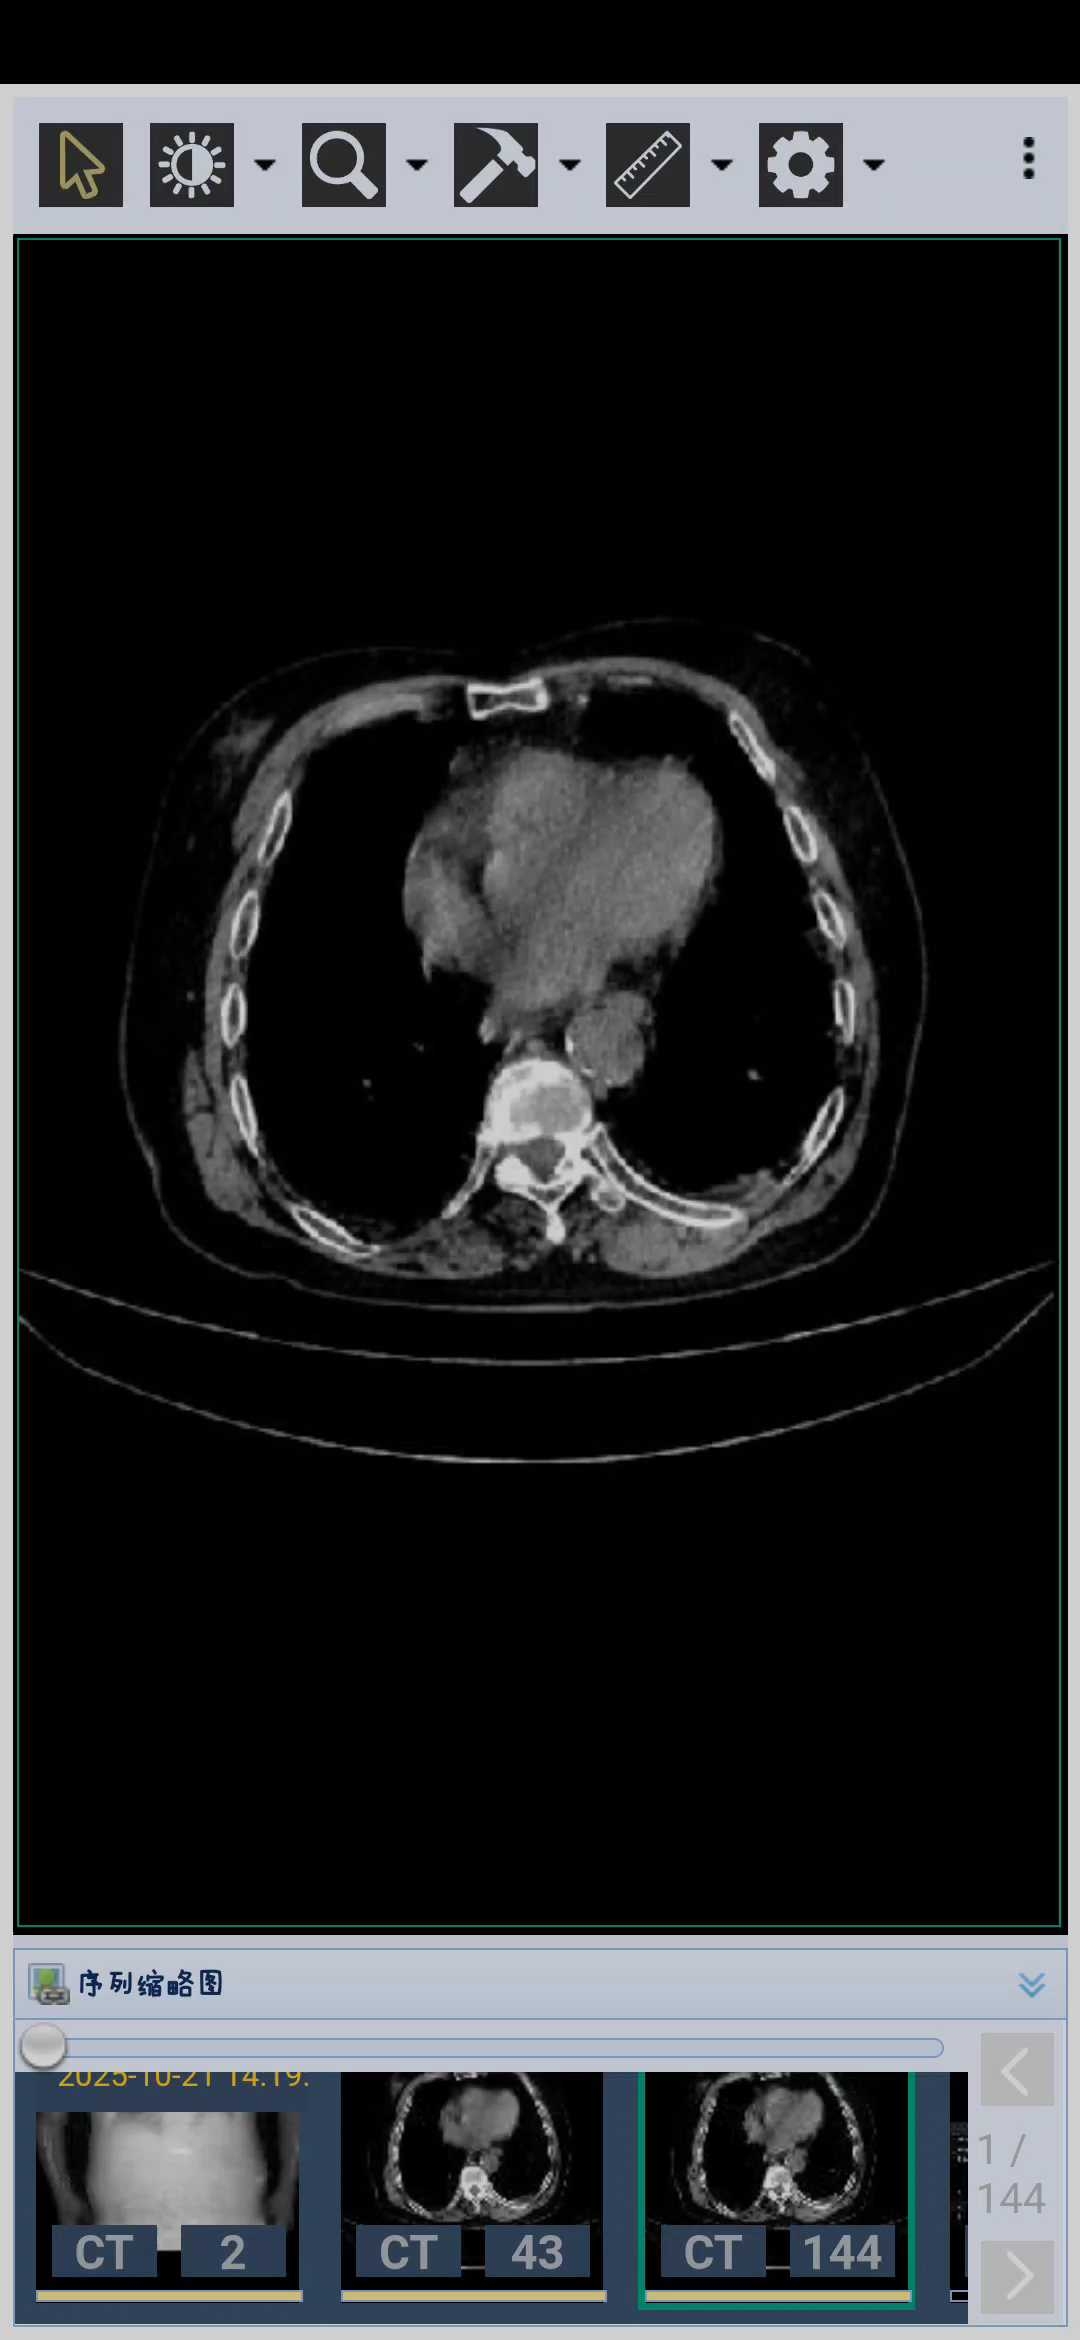

病例85岁老人胆总管扩张的可怕

病例信息